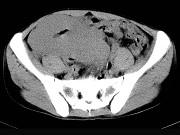

问题 男,23岁,下腹部肿块伴持续性钝痛1月余,影像所见如图,最可能的诊断是()

选项 A.小肠淋巴瘤 B.小肠间质瘤 C.小肠癌 D.小肠转移瘤 E.小肠结核

答案 A